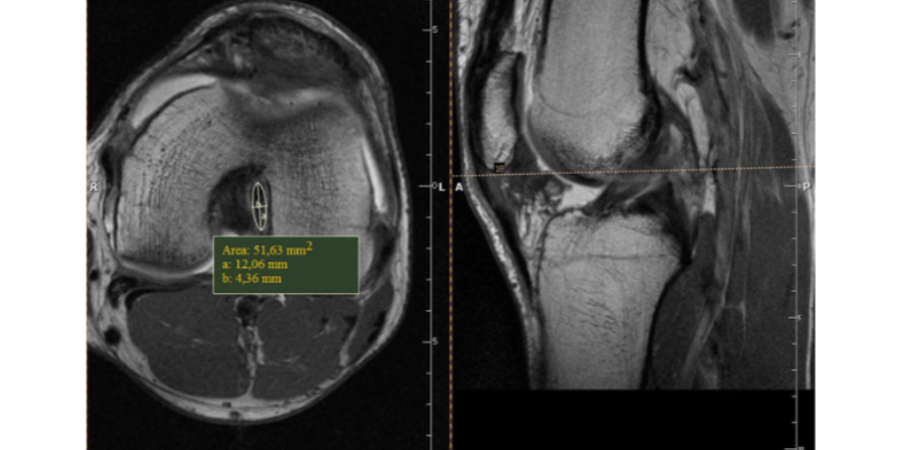

Ein primärer anatomischer Grund für Kreuzbandrisse ist die Dicke des Kreuzbands. Ein sehr interessanter Ausblick zum Thema Hypertrophie (dt. Verdickung) der Kreuzbändern gibt eine Studie (1) von Grzelak et al aus dem Jahr 2012. Diese kam zu dem Ergebnis, dass Krafttraining die Dicke des Kreuzbands um bis zu 350% steigert. In dieser Studie wurde Dicke der beiden Kreuzbänder basierend auf MRT Bildern von Gewichtheber mit denen einen Kontrollgruppe verglichen. Das Ergebnis war ein signifikanter Unterschied. Die Studie war die erste wissenschaftliche Untersuchung, die die Hypertrophie der Kreuzbänder nachgewiesen hat. Ebenfalls wurde festgestellt, das je früher mit dem Krafttraining begonnen wurde, im Idealfall vor der Pubertät, desto größer war der Effekt der Stärkung der Kreuzbändern. Eine Interessante Hypothese der Studie in Bezug auf die Entwicklung der Kreuzbänder ist, dass die Arterie die die Kreuzbänder versorgt (Arteria genus media oder auch „mittlere Kniearterie“) sich im Laufe der Jugend zurückbildet und so die Versorgung der Kreuzbänder mit Nährstoffen bei Kindern und Jugendlichen deutlich besser gewährleistet ist.

Die Ergebnisse der Studie (1) hier:

Ebenfalls führt die Studie als einer der Gründe für diese Hypertrophie der Kreuzbänder an, dass beim Gewichtheben des Knie mit hohen Widerständen über die maximale Beugung belastet wird. Diese maximale Beugung unter hohen Kräfte und die damit verbundene Dehnung der Kreuzbänder aktiviert die Fibroblasten, die die Hypertrophie der Bändern initiieren.

Bild: MRT Bilder der Kreuzbänder (Quelle: siehe Referenz)